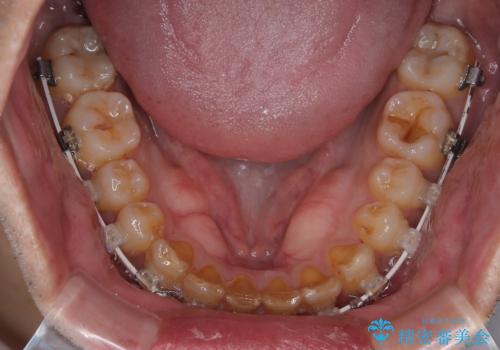

補助装置を用いて、上顎大臼歯を積極的に後方移動させながら、ディープバイトを改善していくこととしました。

強い咬合力に抵抗するため、上下ともに表側のワイヤー装置にて矯正治療を行うこととしました。

上顎歯列を遠心移動させたことで、前歯の叢生が解消されても前歯が前突することなく、左右ともに理想的な咬み合わせを達成することができました。